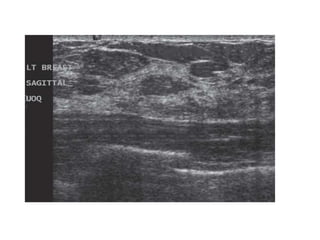

The PET-CT shows diffuse infiltrating carcinoma

Here an exampleof global asymmetry. In this patient this is not a normal variant, since there are associated features, that indicate the possibility of malignancy like thickened septa and subtle nipple retraction. Ultrasound (not shown) detected multiple small masses that proved to be adenocarcinoma. The PET-CT shows diffuse infiltrating carcinoma